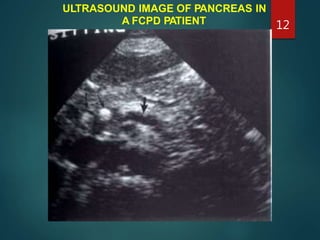

ULTRASOUND IMAGE OF PANCREAS IN

A FCPD PATIENT 12

ULTRASOUND IMAGE OFPANCREAS IN A FCPD PATIENT 12